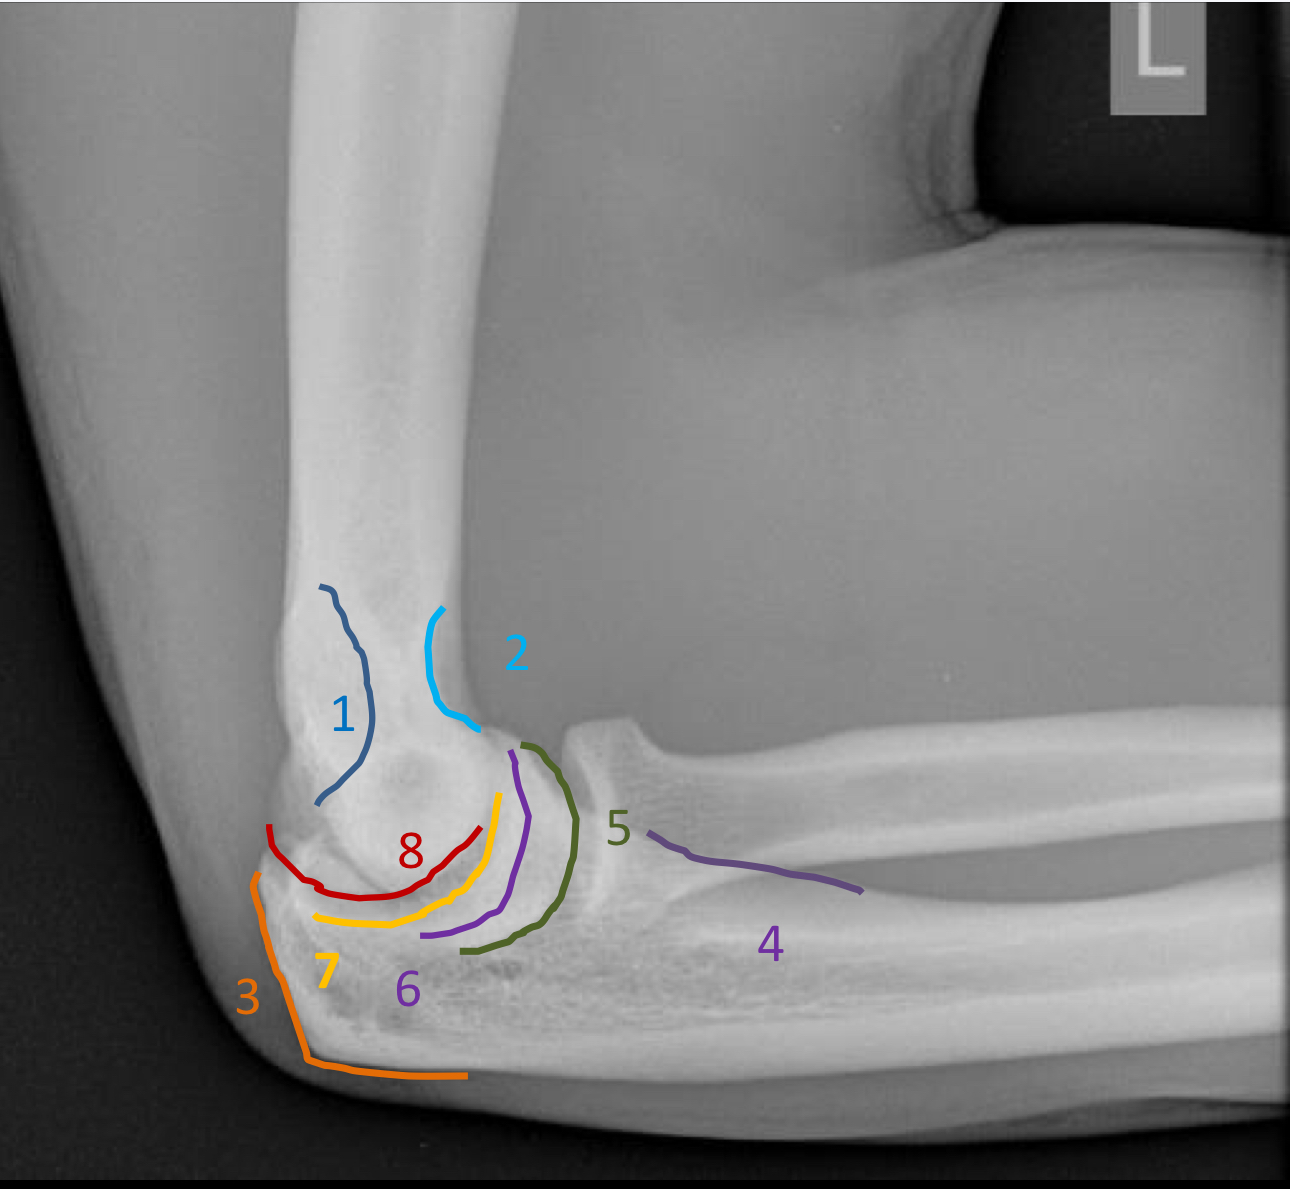

1?

olecranon fossa

2?

coronoid fossa

3?

olecranon process

4?

ulnar tuberosity

5?

capitellum

6?

trochlea

7?

trochlear notch

8?

lateral supracondylar ridge

coronoid process

radial tuberosity

radial notch of the ulna